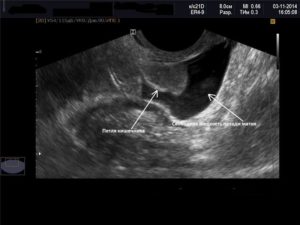

Вода, скопившаяся в позадиматочном пространстве, выявляется во время проведения ультразвукового исследования органов малого таза. Нынешнее оборудование позволяет с максимальной точностью определять её объём.

Жидкость позади матки можно обнаружить при проведении ультразвукового исследования. Чтобы уточнить природу ее происхождения, требуется провести пункцию. Ее делают во время лапароскопической операции.

Свободная жидкость в позадиматочном пространстве диагностируется с помощью УЗИ

С его помощью можно увидеть и распознать даже минимальное количество жидкости как в матке, так и позади нее. Визуально на экране ультразвукового аппарата скопление небольшого количества жидкости напоминает неширокую полоску темного цвета.

Ультразвуковое исследование является одним из самых доступных и достоверных методов, с помощью которого можно обнаружить даже небольшое содержание жидкости в полости малого таза.

На экране УЗ-сканера жидкостные образования за маткой выглядит черного или темно-серого цвета, чаще имеет форму узкой полоски, если ее количество небольшое.

При большом количестве она растекается между органами и принимает неправильную форму.

Точного количества жидкости за маткой в миллилитрах с помощью этого метода определить невозможно из-за того, что жидкость растекается между складками брюшины и органами и не принимает какой-то строгой формы. Тем не менее для описания количества жидкости на УЗИ в полости малого таза существуют определенные критерии.

Врач измеряет наибольшую длину вертикального уровня жидкости за маткой. Если высота уровня жидкости составляет до 10 мм, то ее количество считается незначительным.

Если высота уровня жидкости составляет от 10 мм до 50 мм, то количество ее считают умеренным, более 50 мм – значительным.